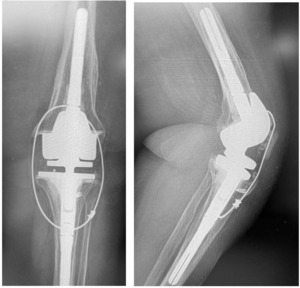

The patellar tendon repair protection technique that I use is a modification of the Shelbourne technique where a 1.7mm cable is used. The cable is not threaded through the patella but rather weaved through the quad above the superior boarder of the patella, allowing for greater tension over time, without pulling through the patella.

Following extensile exposure of the knee, an anchor suture is placed in the proximal tibia for the primary tendon repair. Next, a hole is drilled below the tibial tubercle through the diaphyseal bone, and the cable is passed through the tibia. Once passed through, the wire is laid within the gutters. (Figure 2) Before the cable is weaved through the quad, feel underneath to avoid passing the cable into the joint. (Figure 3) The cable is then weaved through the quad above the patella. (Figure 4) This technique allows for increased early tensile strength to that quad over time. Then, tighten and crimp the cable (Figures 5 & 6) and you bring the tendon together and then perform the repair. When tightening the cable

But how much do you tighten it? Tighten enough when let go against gravity the knee bends between 30 to 45 degrees. (Figure 7) This will allow good tendon repair protection so that they will stretch the quad out over time, and most of them achieve 90 degrees or more.